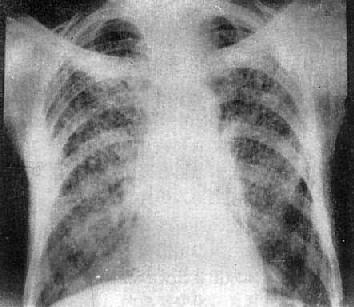

X线表现可多种多样,一般为陈旧性病灶周围炎,多在锁骨上、下区,表现为中心密度较高而边缘模糊的致密影(图3-1-10)。也可为锁骨下区出现新的渗出性病灶,表现为小片云絮状影,范围较大时可呈肺段或肺叶性浸润,症变的发展过程较为复杂,早期渗出性病变可以完全吸收,但一般多呈时好时坏的慢性过程,故可有渗出、增殖、播散、纤维和空洞等多种性质的病灶同时存在(图3-1-24)。

左肺浸润型肺结核空洞形成

图3-1-24 左肺浸润型肺结核空洞形成

左肺上野第2前肋间边缘模糊的致密影,其中可见空洞